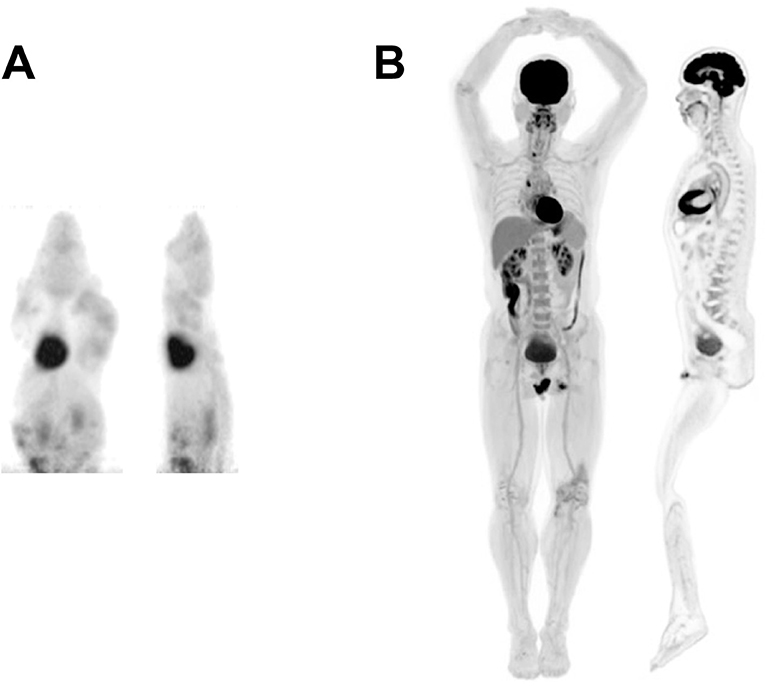

Frontiers | Total Body PET Imaging From Mice to Humans

Total-Body PET Scanner Prototype Due Next Year | Radiology | JAMA …

bone scans of metastatic breast cancer for 60 years old female using …

Early Breast Cancer Detected in an Asymptomatic Female – THE Q INSTITUTE